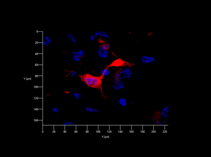

A “core” research team of 2 lab managers is installed at our laboratory to ensure optimal services in developing technical skills of its team members. A variety of standard basic science operations such cell cultures, fluorescence microscopy, Western blot and PCR - just to name some - can be learned at our laboratory.

These images tell a story and we will explain it to you…..